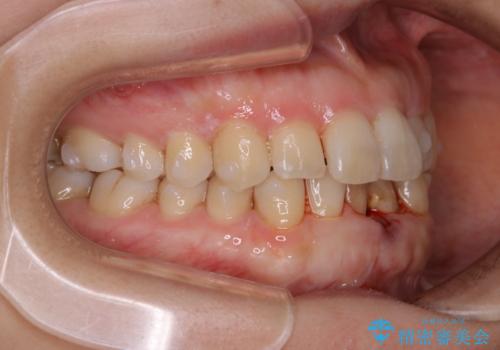

インビザライン・ライトでの抜歯矯正治療 (スリーインサイザー仕上げ)

- 上下の前歯のがたつきが気になるとのことで来院されました。最短治療とインビザラインでの矯正治療をご希望されました。

前歯のがたつきを無くすためには、スペースを確保する必要があります。上の前歯のがたつきは軽度ながたつきのため、歯と歯の間を研磨をして、そのスペースを使い並べていきます。下の前歯は、1本前歯を抜いて研磨せずに、その抜歯したスペースを使い並べることになりました。

下の前歯は、スリーインサイザー仕上げと言って、通常前歯は4本ありますが(犬歯はいれていない)、そのどれか1本を抜歯して前歯を3本にして矯正治療を行うことを言います。また、先天的に歯の本数が少ない方もいますので、矯正治療を行っていなくても元々スリーインサイザーの方もいます。